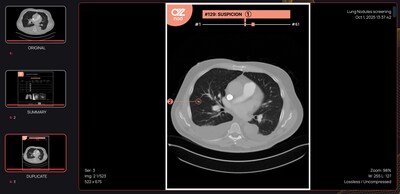

AZnod analyzes each slice of a CT to identify nodules between 3 mm and 30 mm. The system evaluates them, provides measurements of volume, long-axis diameter, and perpendicular diameters, and indicates the exact CT slices where they appear. It then classifies the detected nodules according to density, contour morphology, internal composition, and positioning in the lungs, which supports guideline-aligned clinical assessment without changing existing diagnostic workflows.

The AI model processes images that are strongly pseudonymized and returns structured radiology output to the user. The system provides a single report listing each nodule by clinical priority, with annotated views of size and standardized measurements in millimeters and cubic millimeters, along with its diagnostic attributes, as well as an anatomical lung schematic intended to allow rapid review in the assessment of nodules.